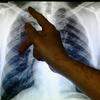

image No Pará 2.710 pessoas foram hospitalizadas em 2021 com quadro de asma. O Brasil é um dos poucos países onde o tratamento é gratuito, feito pelo Sistema Único de Saúde (SUS), como explica o pneumologista Rubens Toffolo (Igor Mota / O Liberal)